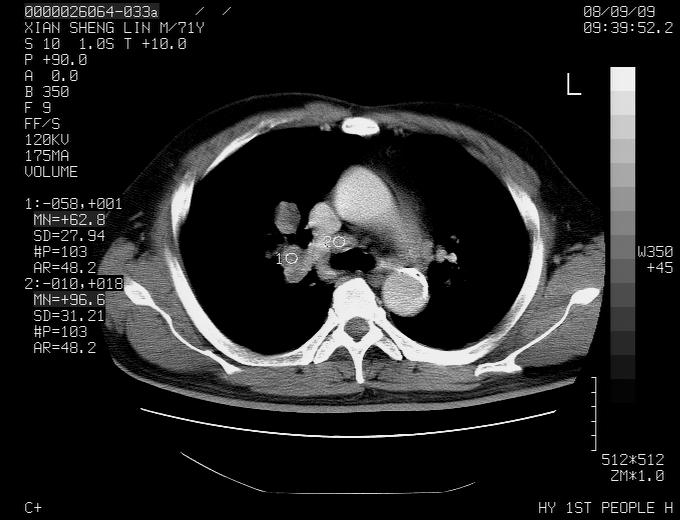

标题: CT15869:男性,71岁,因咳嗽而就诊,请讨论右上肺病变性质 [打印本页]

患者,男性,71岁,因咳嗽而就诊,

典型的右肺中心性肺癌并纵隔淋巴结转移

右肺中心性肺癌并纵隔淋巴结转移可能性大!

病灶中等程度强化 还是支持肺癌诊断

考虑右肺中心性肺癌并右肺门及纵隔淋巴结转移。

1,右肺中心型ca,气管隆突旁淋巴结转移。

2,右膈明显抬高,建议肝脏扫描排除转移或原发灶。